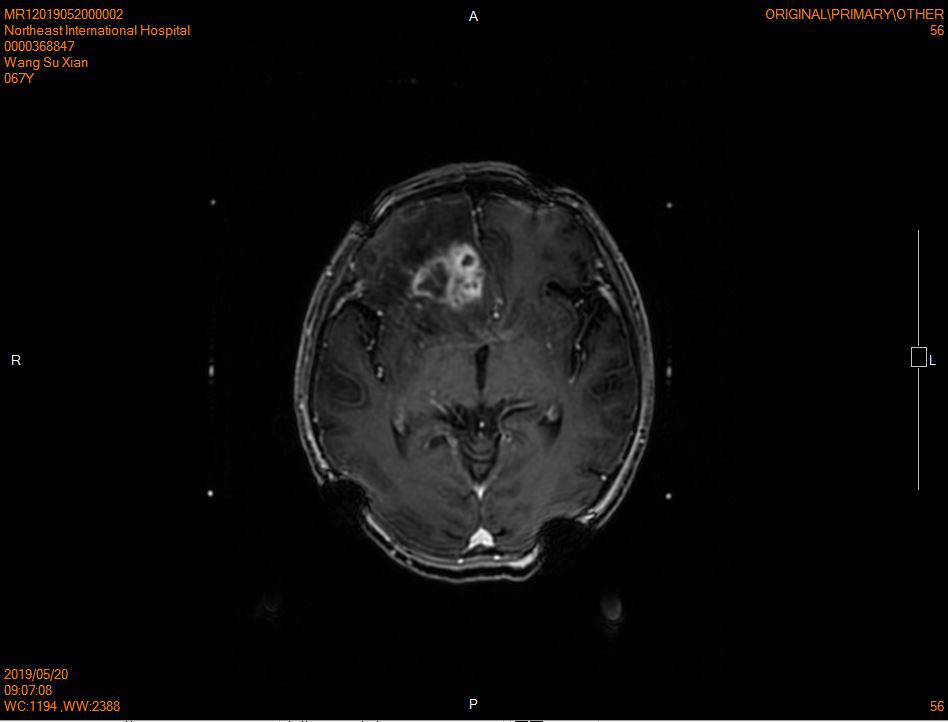

王女士今年67岁,今年5月的一天突然出现癫痫发作,检查头部MRI检查提示:右侧额叶、侧脑室旁多发占位病变,伴右侧脑室受压变窄略向左侧移位,考虑为恶性病变可能性大,多发转移瘤?较大者位于右侧额叶皮层下,范围约3.1*3.1*3.3cm。老人家身体一向健康,面对突入起来的癫痫发作,其儿子更是不敢掉以轻心,四处打听后他了解到针对其母亲的病情,目前治疗脑部肿瘤最好的手段是头部伽马刀。接诊该患者时清楚的记得患者入院时轮椅推入,因头晕而不能行走,表情痛苦。收住院的第二天,殷主任就为患者安排了治疗,治疗后住院观察期间,患者的头晕情况有所缓解,按照出院医嘱,老人家1个月后按时来院复查,刚进病房,看家老人家微笑的脸庞,不再头晕,而且走起路来神采奕奕,复查的头部MRI的结果也令人很满意,肿瘤基本已经消退,治疗头部伽马刀的殷主任说,在3个月内肿瘤还会继续消退的。

治疗前